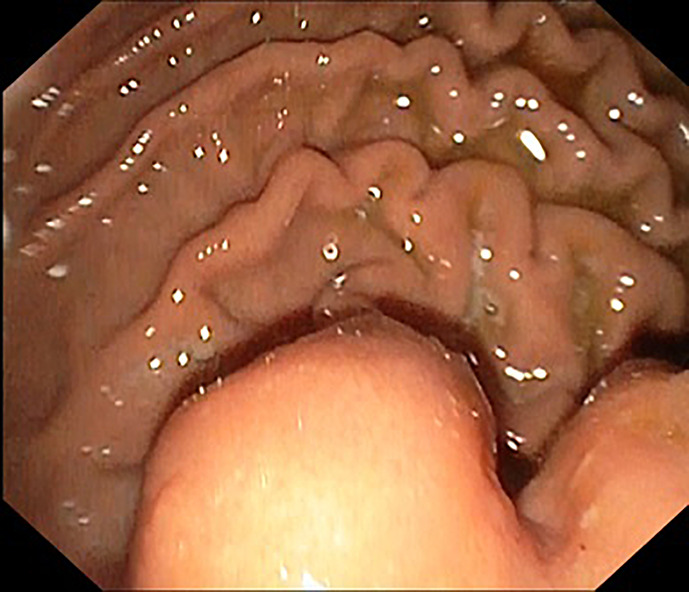

Case presentation: We found a submucosal mass with ulceration in the stomach cardia on esophagoduodenoscopy (EGD). The endoscopic ultrasound (EUS) finding was a hypoechoic submucosal lesion with a clear margin; specimens were taken using fine needle aspiration (FNA) for further histopathological examination. The result indicated granuloma of Mycobacterium Tuberculosis in pathology, suggesting that the diagnosis was gastric TB. The patient was then treated with antitubercular therapy regimen for 9 months. The previously documented mass in the stomach cardia was no longer visible on the follow-up endoscopy examination, and the patient was considered cured.

简介胃肠道结核(TB),特别是胃结核,是一种罕见的肺外结核。由于症状和体征不具特异性,诊断极具挑战性。在本病例报告中,一名 22 岁的男性因反复吐血和便血前来就诊:我们在食管十二指肠镜检查(EGD)中发现胃贲门处有一个粘膜下肿块,并伴有溃疡。内镜超声(EUS)检查发现黏膜下病变呈低回声,边缘清晰;我们用细针穿刺(FNA)取标本进行进一步组织病理学检查。病理结果显示为结核分枝杆菌肉芽肿,提示诊断为胃结核。随后,患者接受了为期 9 个月的抗结核治疗。在随访的内镜检查中,之前记录的胃贲门肿块已不复存在,患者被视为治愈:本病例表明,有胃肠道症状的患者,尤其是生活在结核病流行地区的患者,应考虑胃结核。内镜检查,如胃肠道造影(EGD)和胃超声波检查(EUS),可能有助于胃结核的诊断。